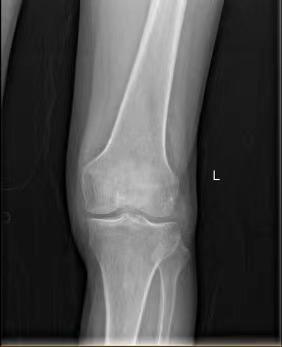

经过详细的体格检查,结合影像学所见,张还添发现黄先生X光片关节间隙尚可,但左膝关节屈伸活动严重受限。进一步磁共振检查发现,黄先生的膝关节可见大量不明物(MRI T2加权显示低密度影),这些坚硬结晶不仅侵蚀软骨与韧带,更形成游离体,直接导致关节不稳与机械性绞锁,保守治疗难以奏效。

X光未见关节间隙明显狭窄及骨赘增生